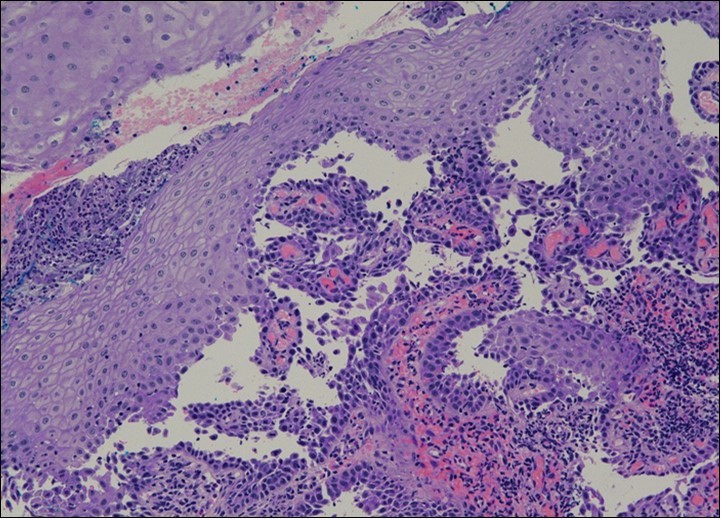

HPV test was negative for high risk subtypes of HPV. The punch biopsy specimen comprised a piece of inflamed cervical tissue in which the transformation zone was represented. The cervical tissue was covered by metaplastic and hyperplastic squamous epithelium showing intraepidermal suprabasal blister formation with acantholysis. Well vascularised dermal papillae lined residual basal cells giving rise to a tombstone appearance were present. There was no evidence of HPV, CIN, CGIN or invasive malignancy.

She was discussed at the hospital cyto-pathology conference to clarify the diagnosis. The original cytological smear specimen was reviewed, with features of bi-nucleation and koilocytosis consistent with LSIL. The cervical biopsy was also reviewed, confirming typical features suggestive of cervical pemphigus. (Figure 4a, Figure 4b, Figure 4c)

Figure 4a.Cervical tissue showing intraepidermal and supra-basal blister formation.